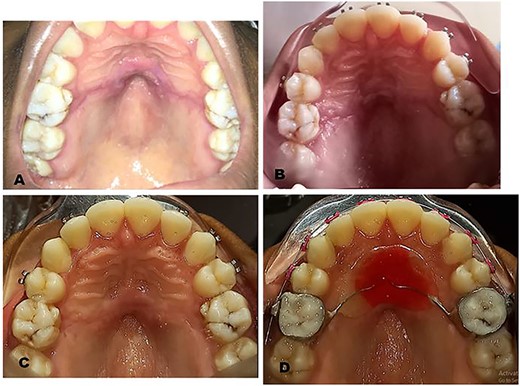

The surgical operation was performed using local anesthesia (LA). Two LA cartridges containing 2% lidocaine were administered on the palate using the subperiosteal infiltration technique. Incision was made on the palatal mucosa following the curvature of the Nance appliance using a No. 15 surgical blade. A partial thickness palatal mucosae flap was raised using a periosteal elevator to expose the buried stainless steel wire and clear acrylic palatal button of the Nance appliance (Fig. 2A). Molar bands on teeth 16 and 26 were removed using a band remover and the periosteal elevator was used to deliver the Nance appliance out of the palatal mucosa (Fig. 2B). The raised flap was repositioned (Fig. 2C) and sutured using black silk suture (Fig. 2D) and hemostasis was achieved by pressure application (patient was asked to bite on gauze for 5 min). The patient was placed on 500 mg amoxicillin, 400 mg metronidazole and 400 mg ibuprofen three times daily for 5 days postoperatively. Postoperative warm saline mouth rinse eight times daily for 2 weeks was also recommended. The patient was followed up 24 h postoperatively (PO), 7 days PO (Fig. 3A), 2 weeks PO (Fig. 3B) and 4 weeks PO (Fig. 3C). Sutures were removed 7 days PO. The patient’s postoperative course was uneventful. A new Nance palatal arch appliance with 0.9 mm hard stainless steel wire loops and the tinted acrylic button was fabricated and patient was fitted with the new Nance appliance 6 weeks PO (Fig. 3D). The patient continued to be on regular follow-up and received further dental and orthodontic treatment.

Intraoperative clinical photographs: (A) Trans-surgical view: partial thickness palatal mucosa flap raised using a periosteal elevator to expose buried Nance appliance. (B) Nance appliance delivered out of the palatal mucosa. (C) Trans-surgical view: raised flap repositioned and showing the outline of incision made. (D) Repositioned flap sutured using black silk sutures.